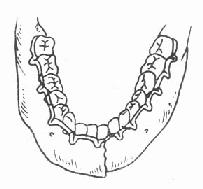

2.牵引复位:颌骨骨折后,经过较长时间(上颌骨三周以上,下颌骨四周以上),骨折处已有部分纤维组织愈合,手法复位不成功,可采用牵引复位法。下颌骨骨折多用颌间牵引,就是在下颌骨有移位的骨折段上安置分段牙弓夹板(图4-16),然后在与上颌的牙弓夹板之间,用小橡皮圈作弹性牵引,使之逐渐恢复正常的咬合关系。上颌骨骨折后,如骨折段向后移位,可在上颌牙列上安置牙弓夹板,在头部制作带有金属支架的石膏帽,在牙弓夹板与金属支架之间作弹性牵引,使上颌骨骨折段向前复位(图 4-17)。需要较大牵引力时,也可作卧式重力性牵引。

| 图4-16 分段式牙弓夹板 | 图4-17 金属支架石膏帽,将上颌骨骨折段向前牵引复 |